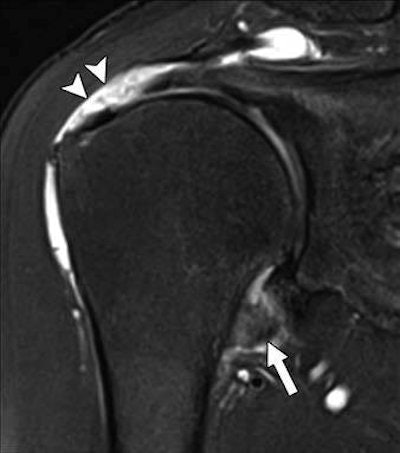

The challenge for physicians is that a physical exam cannot always determine the primary cause of adhesive capsulitis. Hence, MRI becomes the modality of choice to observe joint capsule abnormalities, ligament thickening, tears, and other shoulder anomalies. However, previous research has yet to determine an association between joint capsule abnormality on MRI and shoulder stiffness in patients with rotator cuff tears, Kim and colleagues noted.

The researchers analyzed 106 patients (mean age, 71.2 ± 4.5 years; range, 59-85 years) with full-thickness rotator cuff tears of 5 cm or less. Shoulder MRI scans were performed on either a 1.5-tesla system (Signa HDxt, GE Healthcare) or 3-tesla system (Magnetom Skyra, Siemens Healthineers) with a dedicated shoulder coil. They looked for several shoulder abnormalities, including swelling and thickness in the joint capsule and degeneration of the torn rotator cuff muscle and correlated the MR images with patient's degree of shoulder stiffness, such as their inability to elevate their arms and their restricted range of motion.

Kim and colleagues indeed found significant correlations between patients' limited range of motion, particularly with forward elevation, and thickness of their joint capsule in the glenoid portion and axillary recess of the shoulder. In addition, swelling of the joint capsule in the humeral area of the shoulder was significantly associated with shoulder stiffness and lack of arm elevation.